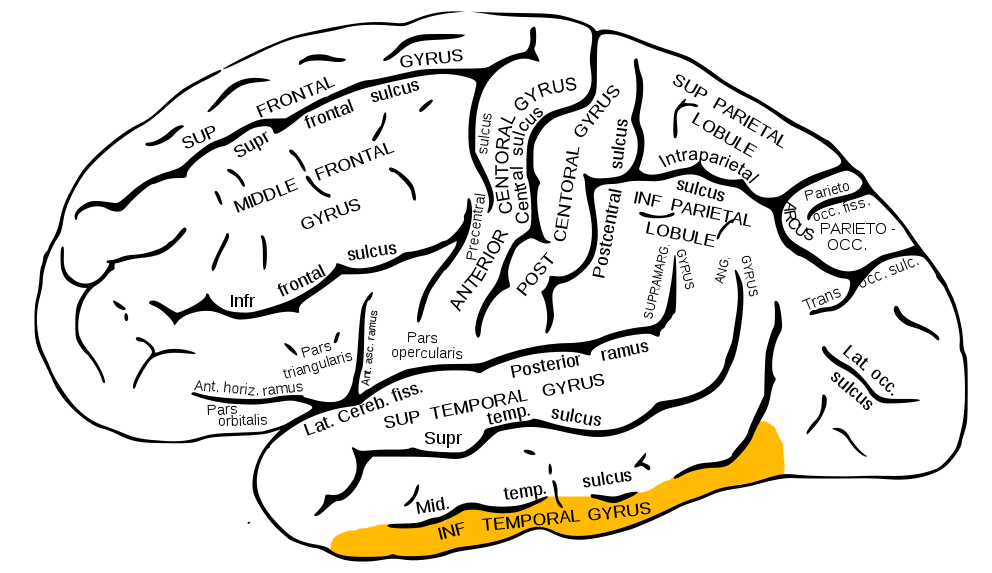

下側頭回 Wikipedia

下側頭回 Wikiwand